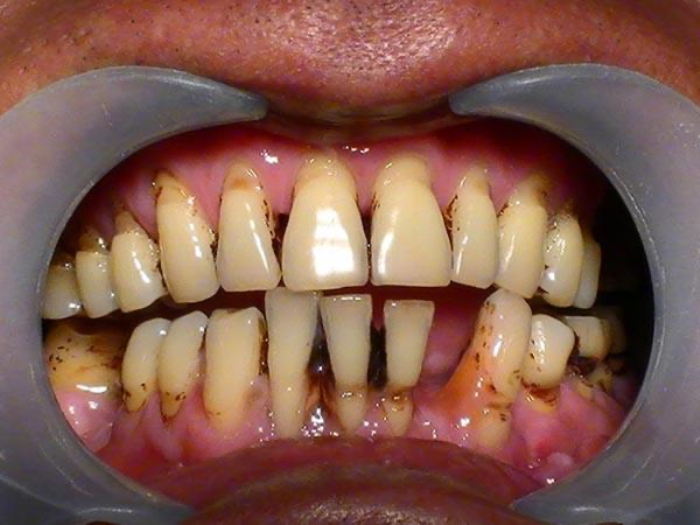

牙齿松动与邻牙间隙变大——牙周病。牙周病是指发生在牙支持组织(牙周组织)的疾病,可以出现进行性附着丧失和牙槽骨吸收,最后导致牙松动丧失。牙周疾病是常见的口腔疾病,是引起成年人牙齿丧失的主要原因之一,也是危害人类牙齿和全身健康的主要口腔疾病。

不注意口腔卫生,食物残渣产生的毒素就会慢慢地刺激牙龈发炎,频繁发炎的牙龈又会刺激到牙槽骨,发炎的牙槽骨慢慢吸收,变得越来越低,包裹它的牙龈也慢慢萎缩,这样暴露在外面的牙根就会越来越多,牙齿就会慢慢松动。也许最开始发现不了,但是当你用力咀嚼食物是会发现上下牙往一起用力时,松动的牙齿被推开一道缝,塞牙就会发生了。